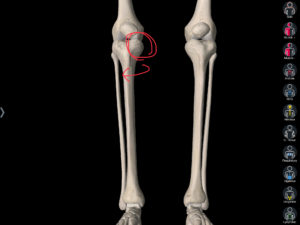

検査をしていると炎症も強く出ていたのですが、膝のお皿の動きが悪く両足の内側の骨が外側に回旋をしていました。

今回の患者さんは膝のお皿の動きが悪くなるにプラスして、膝下の2本あるうちの内側の骨(脛骨/けいこつ)が少し回旋して悪さをしていました。

確認するポイントとしては膝のお皿の横(内側)を少し押してみてください。

↑

(上の赤まるが目印)